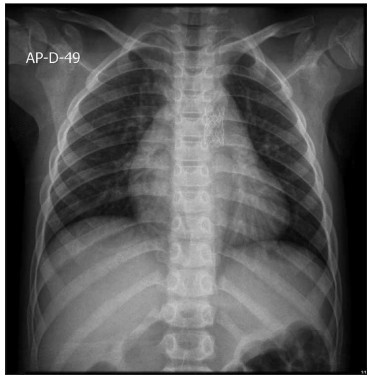

Paciente de 1 ano e 1 mês veio encaminhada, via

CROSS, por cardiopatia congênita. A avó refere que a

criança, desde os 2 meses de idade, fica com a boca roxa

quando chora. Lembra de ter levado a uma UPA, sendo

auscultado um sopro na ocasião e aferida saturação periférica de oxigênio em ar ambiente de 98%. Avó refere,

também, sudorese importante e cansaço às mamadas

com dificuldade de ganho pondo-estatural, além de infecções respiratórias frequentes.

(Arquivo pessoal; imagens usadas com autorização)

Diante do exposto, o diagnóstico correto é: